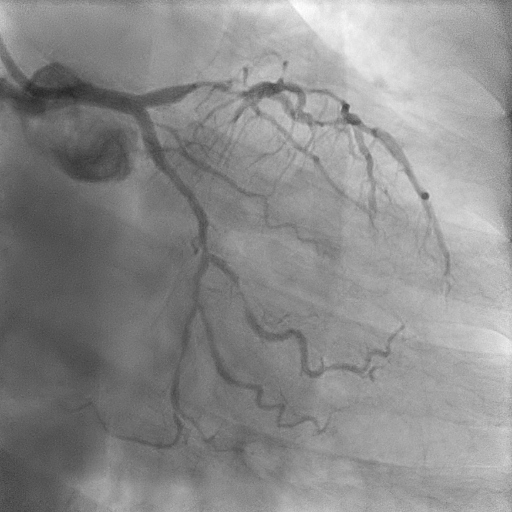

Coronary angiography revealed mild disease of the left main stem. The LAD exhibited severe proximal, mid, and distal disease of a diffuse nature. The LCx demonstrated severe mid–distal disease with a severely stenosed proximal obtuse marginal branch. The dominant RCA showed severe mid-vessel disease with significant involvement of the PL branch.